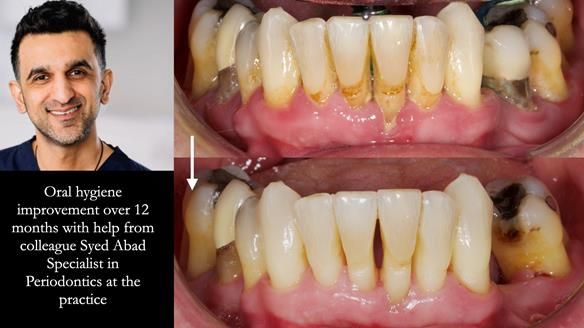

- Periodontal therapy was carried out to help maintain the lower teeth for as long as possible.

- Amazing improvement in oral hygiene and response to Syed’s periodontal therapy.